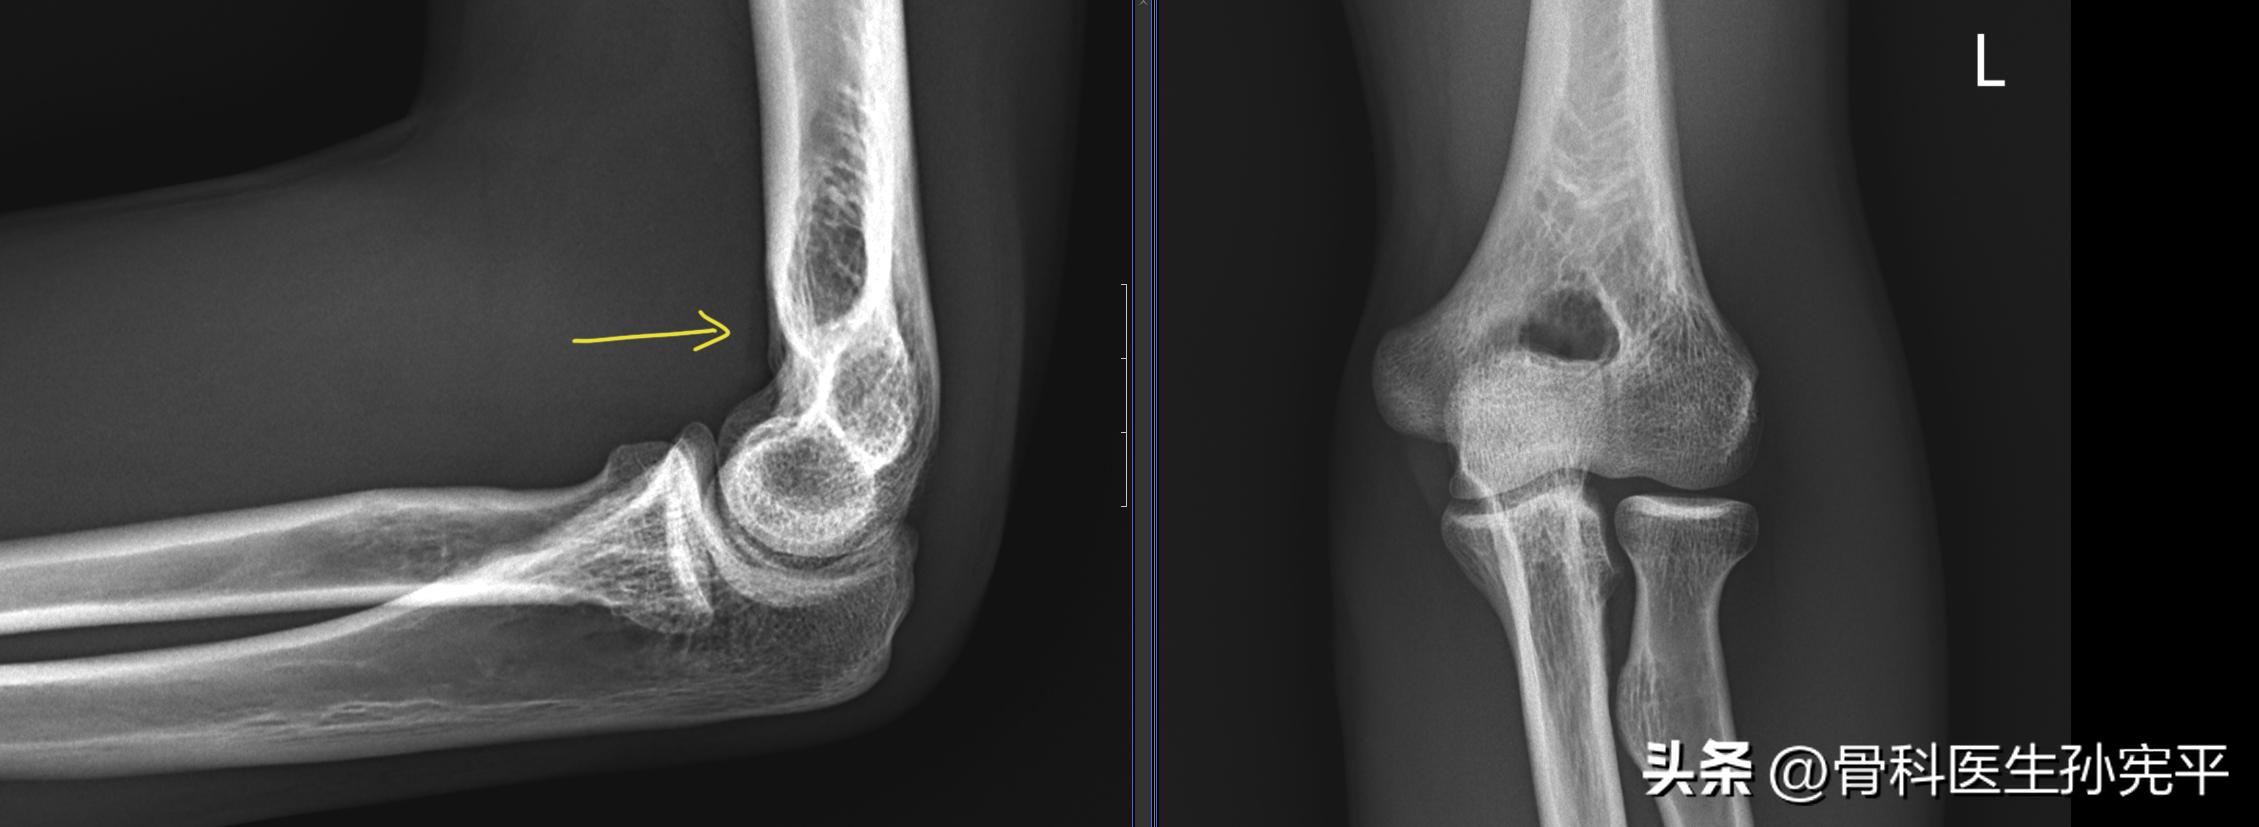

病例4:外伤后左肘关节疼痛2小时

肘关节正常X线片

阅片未见明显异常。对于这张片子我们要着重认识一下肘前脂肪垫。在屈肘90°侧位X线片上,可以清晰显示肘关节前方脂肪垫,呈带状或泪滴状透亮区,宽度约为5mm。若肘前脂肪垫移位或出现肘后脂肪垫征,则强烈提示肘关节损伤。